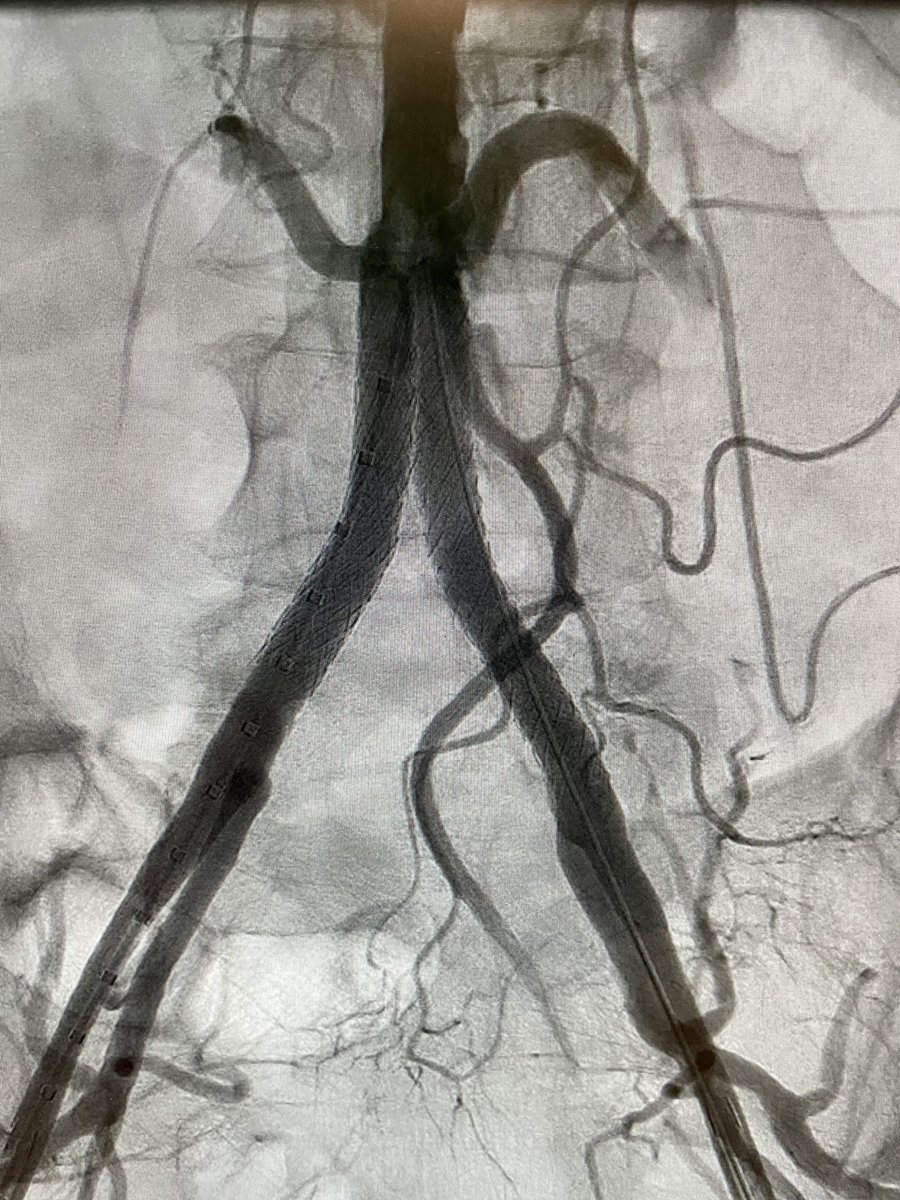

Here is some food for thought regarding the treatment of patients with intermittent claudication and iliac artery disease. #EJVESvisualabstract Full text #openaccess in: ejves.com/article/S1078-… #EJVESforum #EJVESEditorsChoice Melina Vega bazinger_z

Here is some food for thought regarding the treatment of patients with intermittent claudication and iliac artery disease.